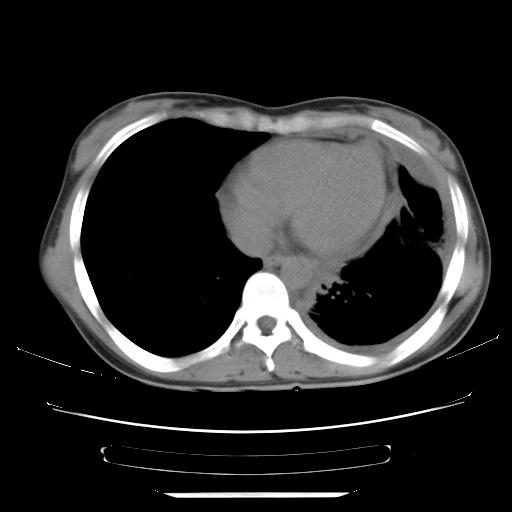

标题: CT21561:外院胸片提示胸腔积液,行CT检查。 [打印本页]

女,29岁,胸部不适,在外院胸片提示胸腔积液,到我院ct检查。

纵膈窗

1、左侧包裹性积液伴叶间积液 2、右肺多发结节考虑增殖结节

左侧纵隔胸膜包裹性积液、左侧胸腔积液、胸膜肥厚粘莲,考虑结核性胸膜炎

左肺上叶不张,左侧胸水,叶间裂积液,纵隔淋巴结,脾脏钙化,考虑左肺上叶支气管内膜结核,结核性胸膜炎,脾结核

考虑:1.两肺tb;2.左侧胸膜炎、胸腔积液。

考虑两肺结核,左侧包裹性积液,叶间积液。

支持两肺继发性肺结核,左侧胸膜腔包裹性积液、胸膜肥厚,脾内多发钙化(结核钙化)。

右肺多发结节。左胸腔多发包裹性积液。